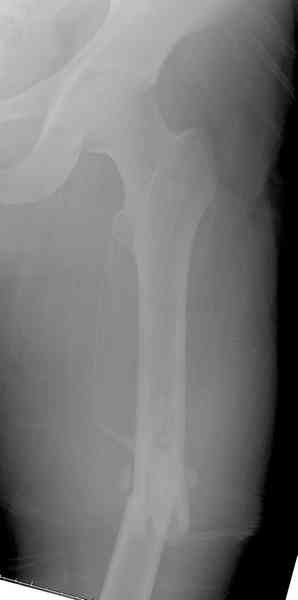

Предыдущей сменой до 4:00 утра по поводу открытого перелома бедра, тибиал плато, пилон и надколенника сделана операция.

Пострадавшему 21 г., травма скоростная, после I&D с расширением раны, на бедре сделана операция ретроградным интрамедуллярным штифтом, остеосинтез с частичной резекцией надколенника и ушивание собственной связки.

На голень наружный фиксатор, рану на бедре ушили (рана была изнутри кнаружи всего 2 см). По протоколу травматических больных, до операции обследован ангиографически, (у больного дистально не смогли определить пульсацию) сосудистый хирург подтвердил проходимость на всем протяжении магистрального сосуда нижней конечности по снимкам ангиограмм.